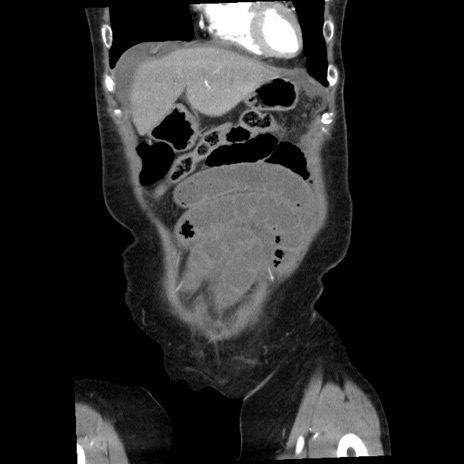

症例1(冠状断像)

【症例】80歳代女性

【主訴】腹痛

【現病歴】8時間前から腹痛あり来院。

【既往歴】糖尿病、脂質異常症、子宮体癌にて子宮全摘術

【身体所見】意識清明・会話良好だが腹痛で苦悶様、全腹部にわたって反跳痛と圧痛あり

【データ】WBC 13600、CRP 0.14、LDH 224、CK 90